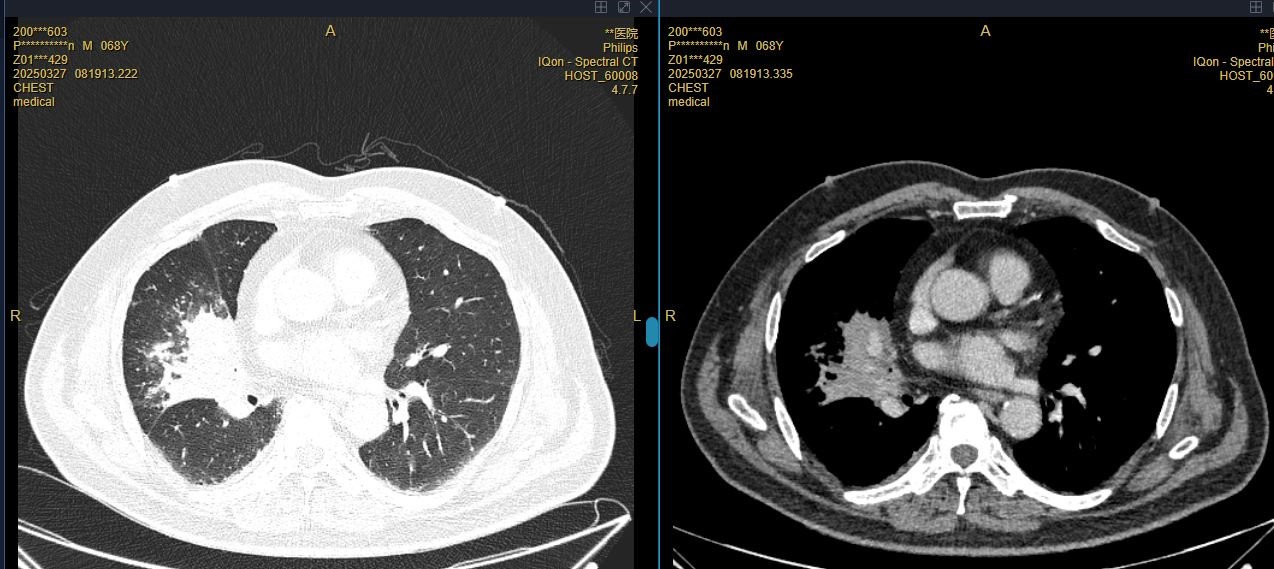

患者彭先生,因咳嗽一月余,加重伴发热2周入院。1月前出现咳嗽,较剧烈,伴有明显呛咳,患者未予重视;2周前咳嗽症状较前加重,伴咳较多黄浓痰,呛咳明显,咳嗽后胸闷气急较前加重,遂至外院就诊,查胸部CT示右肺中叶炎症,心脏增大。入院后余抗感染治疗后仍有反复发热,复查增强CT右肺中叶不张伴阻塞性肺炎,较前明显进展。3月28日在外院行支气管镜检查,见右肺中叶异物堵塞管腔,住院期间多次尝试取出异物,却因种种困难未能成功。回顾病史,患者不仅有脑梗塞、高血压等基础疾病,还曾经历颅脑外伤、腰椎手术、气管切开术,既往手术麻醉后出现谵妄,麻醉风险极高,为手术增添了重重阻碍。